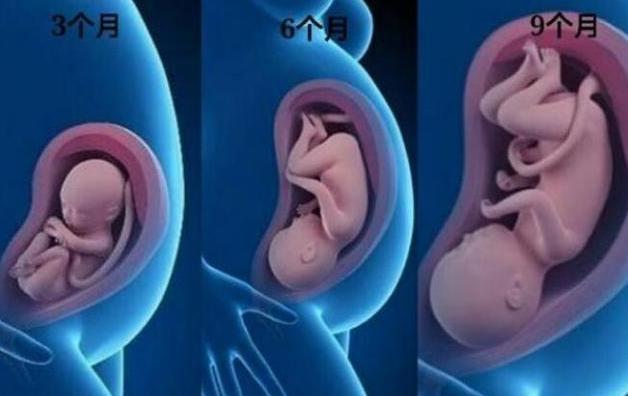

有人说,女性在分娩时是最大、最高级的痛苦,其实,在怀孕的过程中也是很难熬的。尤其在孕期的这三个阶段:孕3个月、孕6个月和孕9个月。也许很多人不理解为什么是这三个阶段,其实这三个阶段非常有特点,至于它们之间有何不同,下文会给您详细的答案!

在前3个月时,尽管胎儿在妈妈的肚子里动来动去,但是孕妇一般是感觉不到的。到了3个月之后,孕妇的身材会有些明显变化了,肚子能看到隆起的样子了,因为这时候胎儿已经长大了。通常,3个月大的胎儿为15g左右,身长就是10cm左右,如小手掌般大,所以,这时候的孕肚还不会给孕妇的生活带来很大的影响。

到了6个月时,胎宝宝的成长速度很快了,已经有700g左右了,身长也是3个月前的3倍。这时,孕妇的肚子会比较明显了,因为胎儿在子宫占据了很大的空间。另外,孕妇也能感觉到胎动了,不过,这时的胎儿的动作不是很有规律,随时都会在妈妈的肚子里进行拳打脚踢,因此,孕妇时常会有不适感。但是又摸不准胎动的规律,所以孕妇才会心生烦躁,甚至晚上也睡得不安稳。这时段是孕妇心理压力最重的时候,家人们一定要多创造愉快的氛围,让孕妇开心度过这段时间。

快到9个月时,孕妇的身材和生活都会发生很大的变化。因为这时的胎儿把妈妈的肚子已经撑得很大了,孕妇24小时都需要挺着大肚子。此时,胎儿在妈妈的肚子里也表现出不安分的样子,经常动来动去,让妈妈不能好好休息,所以常常会感觉到疲劳。而到了9个月时,孕妇是要快接近分娩了,这时的胎儿在妈妈的子宫里可算是一个庞然大物,而胎动的频率也会慢慢变小。不过,孕妇不可以放松警觉,因为胎儿有可能会因活动受限而出现异常。这个时期的孕妇,因为胎儿庞大的原因,也会出现一些疼痛感,另外,孕妇的食欲会有所下降,以及会出现不自觉的郁闷心情,这时需要家人帮助及时疏导。